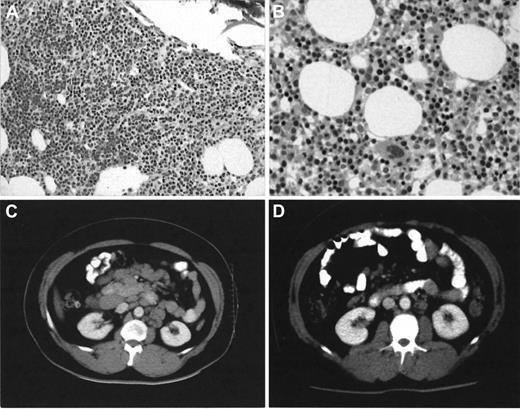

Five of 6 patients with advanced stage B-CLL who failed to respond to fludarabine or to Campath-1H when administered as single agents responded significantly better (1 complete and 4 partial responses) to both agents used in combination. Five patients are alive at a median follow-up of 12 months (range of follow-up, 8-16 months). Marrow trephine appearances normalized in 3 patients (UPN1, 3, and 5). Two of these patients (UPN1 and 5) had no detectable disease by MRD flow. Two other responders (UPN4 and 6) had hypocellular trephines with 0.8% and 0.35% clonal B cells detected. Complete resolution of massive lymphadenopathy occurred in UPN3 (Figure1). Toxicity during combined therapy was acceptable with only one patient (UPN5) requiring hospital admission with pseudomonas bronchopneumonia during neutropenia. No interruption occurred in any other patient. Two neutropenic patients responded to granulocyte colony-stimulating factor and no patients required platelet transfusions. No CMV reactivation occurred. Two patients (UPN1 and 3) have successfully undergone autologous PBSCT with stem cells collected after combined therapy.

Bone marrow trephine and CT scan appearances in patient UPN3 before and after combined Campath-1H and fludarabine therapy.

Note heavy infiltrate (A) × 10 by small lymphocytes observed after 16 weeks of single-agent Campath-1H has completely cleared (B) × 20 with normal erythropoiesis evident after combined Campath-1H and fludarabine. Stained with hematoxylin-eosin. The CT scan (D) shows almost complete radiologic resolution of his previously massive lymphadenopathy (C).